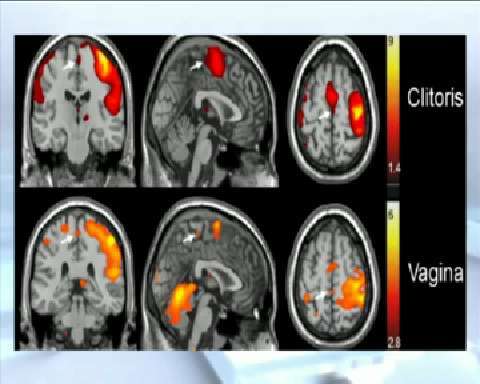

Para averiguarlo ha sometido a decenas de mujeres a una prueba en un escáner y les ha hecho una resonancia magnética en plena excitación sexual . Las manchas rojas son las partes del cerebro que se activan cuando se estimula el clítoris o la vagina. Cada uno manda información a un sitio distinto del cerebro.